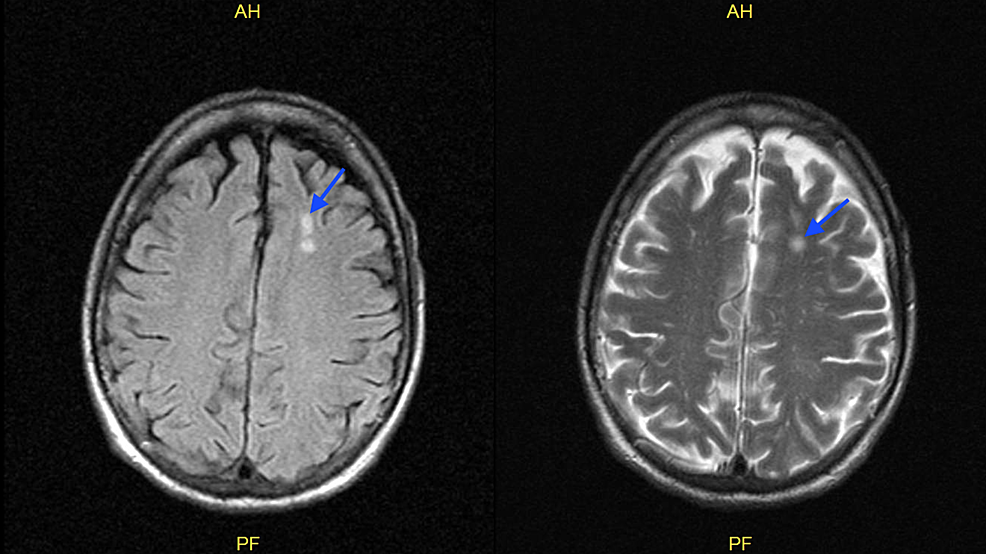

A presumptive diagnosis of disseminated VZV with encephalitis was made according to the patient's skin lesions and CSF analysis. Therefore, he was started on intravenous acyclovir at 10 mg/kg every eight hours and admitted to the general medical floor under contact and airborne precautions. Patient’s varicella zoster PCR from the CSF sample came back positive. Patient mental status improved rapidly within 48 hours of treatment and he became alert and fully oriented. On eye exam, the patient had diplopia with right gaze, and it was determined that he had a right sixth cranial nerve palsy. He had deficits in right sided cranial nerves VI, VII, and VIII evident by impaired right eye abduction, right sided facial weakness, as well as impaired hearing. This constellation of findings is likely secondary to Ramsay Hunt syndrome with multiple cranial nerve involvement. Intravenous acyclovir was continued, and the patient started taking prednisone 50 mg orally for five days for the treatment of Ramsay Hunt syndrome. He was also found to have otitis externa and was prescribed ciprofloxacin with dexamethasone otic drops. Magnetic resonance imaging of the brain without contrast found nonspecific white matter lesions in the high left frontal lobe measuring approximately 8 mm but otherwise no mass, hemorrhage, or acute infarct (Figure 3).